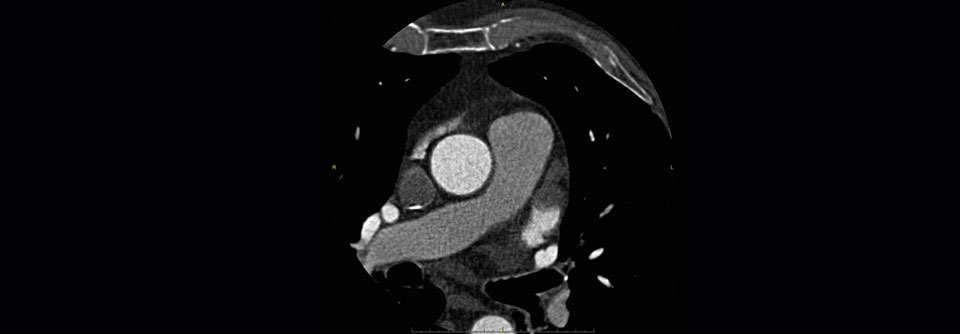

Trotz Antikoagulation entwickeln Betroffene mit nicht valvulärem Vorhofflimmern häufig Thrombembolien. In diesen Fällen könnte der Verschluss des linken Vorhof-Ohres helfen.

Menschen mit Vorhofflimmern, die trotz oraler Antikoagulation einen Schlaganfall erleiden, tragen ein hohes Rezidivrisiko. Eine mechanische Prophylaxe durch Verschluss des linken Vorhofohrs könnte den Betroffenen einen zusätzlichen Schutz verleihen. Eine europäische Forschungsgruppe untersuchte die präventive Wirkung dieser Maßnahme in einer Studie.